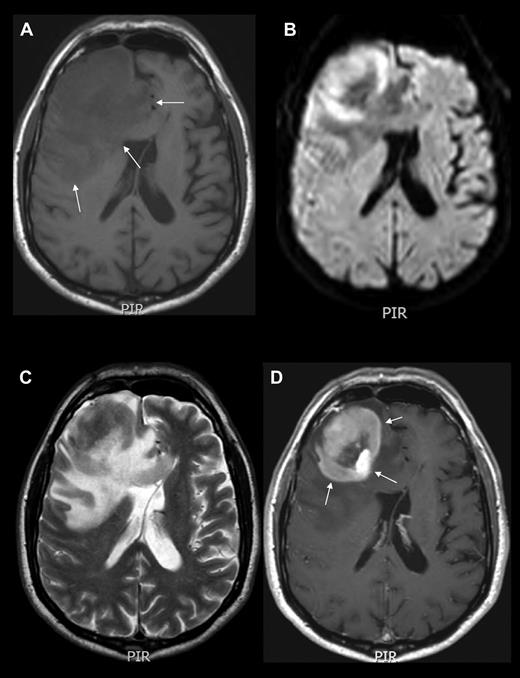

The above-mentioned symptoms usually lead to neuroimaging assessment. Contrast-enhanced cranial magnetic resonance imaging (MRI) is the best imaging modality for assessing PCNSL patients. Lesions are often isointense to hypointense on T2-weighted MRI, with variable surrounding edema and a homogeneous and strong pattern of enhancement (Figure 1–2).6 In cases of MRI contraindications, contrast-enhanced cranial computed tomography (CT) scans are recommended. PCNSL presents as a solitary intracranial mass lesion in 60%-70% of patients, mostly located in the hemispheres, basal ganglia, corpus callosum, and periventricular regions (Figure 1). Gliomas, metastases, toxoplasmosis, sarcoidosis, and progressive multifocal leukoencephalopathy are the main differential diagnoses, requiring brain biopsy for definitive diagnosis.

Neuroimaging example of PCNSL. MRI of the brain showing an expansive mass lesion in the right frontal lobe, which is hypointense in noncontrasted T1 scans (A), isointense with respect to cortex in T2-weighted images (C), with reduced average diffusion coefficient (B), and homogeneous contrast enhancement in contrasted T1 weighted scans (D arrows). Lesion is surrounded by modest edema (A arrows). CT and MRI findings are attributed to the high cell density and scant cytoplasm. Enhancement along the Virchow-Robin spaces, although not constant, is a highly specific feature of PCNSL.